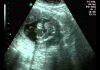

Forside Video 2D Scanning video uge 18+4 uge 18+4 Af MinGraviditet Redaktion 1295 Uge 18+4 Lagt på siden af Charlotte D. 26. juni 2007 Artikler om graviditet Mad og Graviditet – Hvilken kost bør du spise når du... MinGraviditet Redaktion - april 15, 2016 0 Hvilke mad- og drikkevarer bør der indgå i din kost under din graviditet, og hvilke skal du helst undgå? Her får du en liste over udvalgte fødevarer Stor guide til graviditetsundersøgelser når du er gravid april 15, 2016 Graviditetssymptomer og almindelige problemer der kan opstå i en graviditet april 15, 2016 Stor tema om graviditet med masser af gode råd april 15, 2016 Spørgsmål om graviditet Må jeg spise chilli når jeg er gravid? Lone Mørk - maj 8, 2016 0 Der er en del madvarer man skal holde sig fra når man er gravid men er chilli en af dem? En bruger spørger : Må jeg spise chilli når jeg er gravid? Kan zoneterapi hjælpe på vand i kroppen når man er gravid? maj 8, 2016 Må jeg gå til tandlæge når jeg er gravid? maj 8, 2016 Spørgsmål om fødsel Jeg har mange plukveer. Hvad er risikoen for at føde for... Eva Maria Vammen - maj 8, 2016 0 Jeg har mange plukveer. Jeg gik til læge som konstaterede at jeg havde blød livmoderhals. Hvad er risikoen for at føde for tidligt? Går en igangsat fødsel hurtigere hvis man har født før? maj 8, 2016 Jeg føler der hænger noget ud af mit underliv efter fødslen.... maj 8, 2016 Kan der opstå komplikationer ved en fødsel pga. for lavt blodtryk? maj 5, 2016 Er der noget man skal være særlig opmærksom på ved fødslen? maj 5, 2016 Graviditetsberetning Kirstens anden graviditet – en graviditetsdagbog MinGraviditet Redaktion - april 23, 2016 0 Uge 0 - 4: 30. juni - 27. juli 2006 Jeg venter på at min menes skal komme. Jeg har slet ingen fornemmelse om den... 3. trimester – Flytning sidst i graviditeten april 23, 2016 3 trimester – min gravide mave er rimelig stor april 23, 2016 Fødselsberetning Ann´s første fødsel MinGraviditet Redaktion - maj 11, 2016 0 Du får nu mulighed for at læse (næsten) alt om Roberts fødsel! Der er måske nogle detaljer, som du godt kunne have undværet, men jeg... Dorits fødselsberetning maj 11, 2016 Tobias bliver født 5 uger for tidligt april 23, 2016